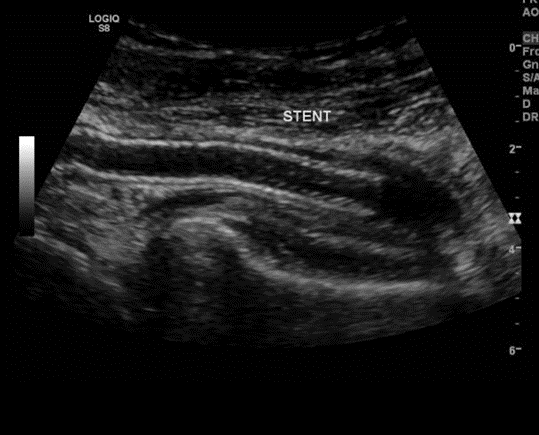

Figure 1: Angio-CT scan in axial incidence showing popliteal artery aneurysm (PPA).

The patient was scheduled to undergo endovascular treatment of the popliteal artery aneurysm. Under general anesthesia, a right common femoral artery was antegrade punctured guided with a duplex ultrasound to perform the whole intervention percutaneously with a 6F 11cm sheat. After the puncture, the Perclose Proglideâ was inserted, in order to preload and guarantee the sealing of the puncture. Then, a 0,035”260cm Terumo â was used to perform the crossing over the distal arteries. The patient was heparinized with 5000UI intravenous in bolus. We performed a right limb arteriography to confirm the popliteal artery aneurysm (Figure 2). The popliteal artery was properly catheterized and we changed the guidewire for an Amplatz 0,035”260cm, in order to place a 11cm 11F sheat. After proper evaluation, two a covered self-expandable 8x100 and 10x75 Merit Wrapsodyâ were placed under roadmap into the distal popliteal artery and proximal femoral artery respectively, and post dilatated with a 8x100 and 10x100 catheter balloon Oceanus figures 3 and 4. There were no endoleaks, and the popliteal artery patency was identified. All the materials were removed, and we completed the final step of the perclose Proglideâ puncture closing. The patient was transferred to the nursery room, being discharged from the hospital two days after the surgery with no complications, femoral, popliteal and podal pulses present bilaterally, taking Rivaroxaban 20mg / day and Clopidogrel 75mg/day. After 1 month the patient was evaluated, presenting no further symptoms, no palpable mass in the right popliteal artery, and was submitted to a Duplex Ultrasound (Figure 5), that showed deep popliteal artery patency, stent patency, reduction of the aneurysm sac and no endoleaks. Furthermore, after one year follow-up, the patient remained asymptomatic, with Duplex Ultrasound showing popliteal artery with stent patency and no endoleaks. (Figure 6).

Figure 5: Duplex Ultrasound showing popliteal artery patency, stent patency and no endoleaks at 1 month.

Figure 6: Duplex Ultrasound showing popliteal artery patency, stent patency and no endoleaks at 1 year.